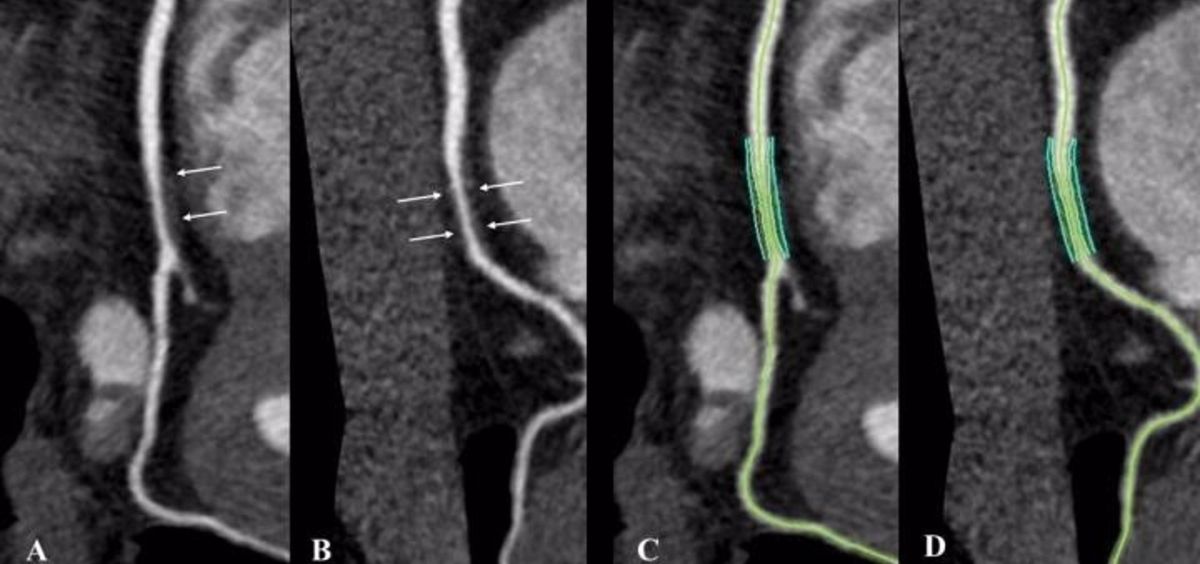

La mayoría de los participantes también se sometieron a una angiografía coronaria por TC, una opción de imagen no invasiva capaz de cuantificar y caracterizar la placa coronaria y predecir el riesgo de eventos cardiovasculares adversos como un ataque al corazón. Los evaluadores de imágenes, que no conocían las características clínicas de los participantes ni su estado serológico, utilizaron los resultados de la angiografía por TC para clasificar las placas coronarias como calcificadas, no calcificadas o mixtas.

Sin embargo, la prevalencia y el volumen de la placa no calcificada fueron de dos a tres veces mayores en la angiografía coronaria por TC en las personas con VIH en comparación con los voluntarios sanos no infectados por VIH, tras el ajuste por factores de riesgo cardiovascular. La placa no calcificada puede ser más propensa a romperse que la calcificada.

"Nuestro estudio muestra que la placa coronaria no calcificada aumenta en las personas con VIH --afirma el autor principal del estudio, el doctor Carl Chartrand-Lefebvre, del Departamento de Radiología del Centro Hospitalario de la Universidad de Montreal (CHUM)--. Y se ha demostrado previamente que la placa no calcificada se asocia con peores resultados cardiovasculares que las placas calcificadas o mixtas".

"Para los radiólogos, estos resultados sugieren que la interpretación de la angiografía coronaria por TC en las personas que viven con el VIH debería incluir probablemente la cuantificación de la placa coronaria por subtipos para permitir una mejor estratificación del riesgo cardiovascular", explica el doctor Chartrand-Lefebvre.